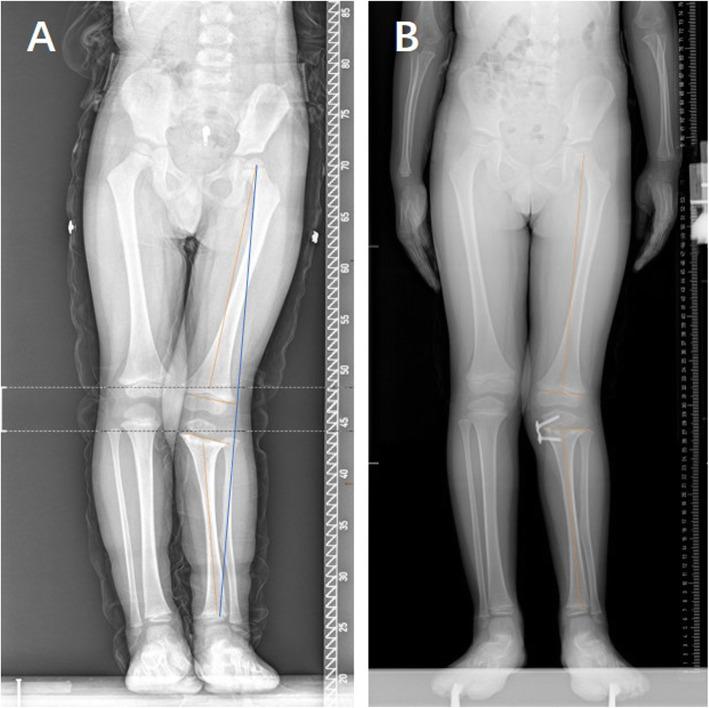

Temporary hemiepiphysiodesis (TH) using an eight-Plate implant is one of the most common surgeries used for the correction of coronal angular deformities around the knee in adolescents. However, few studies have focused on children aged less than 10 years treated with TH using an eight-Plate implant. The purpose of this study was to investigate the efficacy, correction velocity, and complications of TH with an eight-Plate implant as well as the occurrence of rebound and risk factors in this population.

This retrospective study included a total of 135 physes (101 knees) from 66 children (mean age of 4.69 years old, range from 1 to 10 years old) who underwent TH with an eight-Plate implant to correct coronal genu angular deformities in our hospital. Related clinical factors were recorded and analysed by multivariable linear and logistic regression models.

The mean deformity correction period was 13.26 months, and the mean follow-up after eight-Plate removal was 12.71 months. In all, 94.06% (95/101 knees) of the genu angular deformities were completely corrected. Non-idiopathic genu angular deformity was found to be an independent risk factor for deformity correction failure (odds ratio (OR) = 2.47). The femoral correction velocity was significantly higher than the tibial correction velocity (1.28° vs. 0.83° per month, p < 0.001). After adjustment for other factors, younger children had higher correction velocities in the distal femur; however, genu valgum and idiopathic deformities were associated with higher correction velocities in the proximal tibia. In addition, we found three (3/101, 2.97%) knees with genu valgum that experienced rebound after removal of the eight-Plate, while five (5/101, 4.95%) knees with non-idiopathic genu angular deformity experienced screw loosening. No other complications were found, and non-idiopathic deformity was the only risk factor for complications (OR = 3.96). No risk factor was found for rebound in our study.